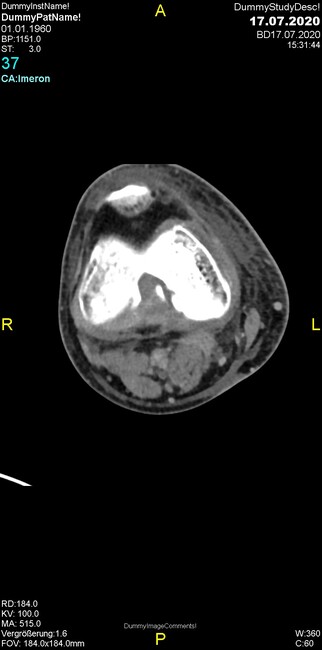

Um welche Modalitäten handelt es sich?

- Röntgen p.a. und lateral, CT coronar Knochenfenster, CT axial Weichgewebsfenster

- Röntgen p.a. und oblique, CT coronar Knochenfenster, CT axial Weichgewebsfenster

- Röntgen p.a. und lateral, CT sagittal Weichgewebsfenster, CT coronar Knochenfenster

- Röntgen p.a. und oblique, CT sagittal Knochenfenster, CT coronar Weichgewebsfenster

- Röntgen p.a. und lateral, CT coronar Weichgewebsfenster, MR axial

Was fällt in der CT im Knochenfenster auf?

- Mediale Gelenkspaltverschmälerung

- Dezente Erosion der fibulären Kortikalis

- Frakturspalt der lateralen Tibiametaphyse

- Weichgewebskalzifikationen lateral angrenzend an den Gelenkspalt

- Osteolyse der Tibiametaphyse unter Beteiligung der Kortikalis